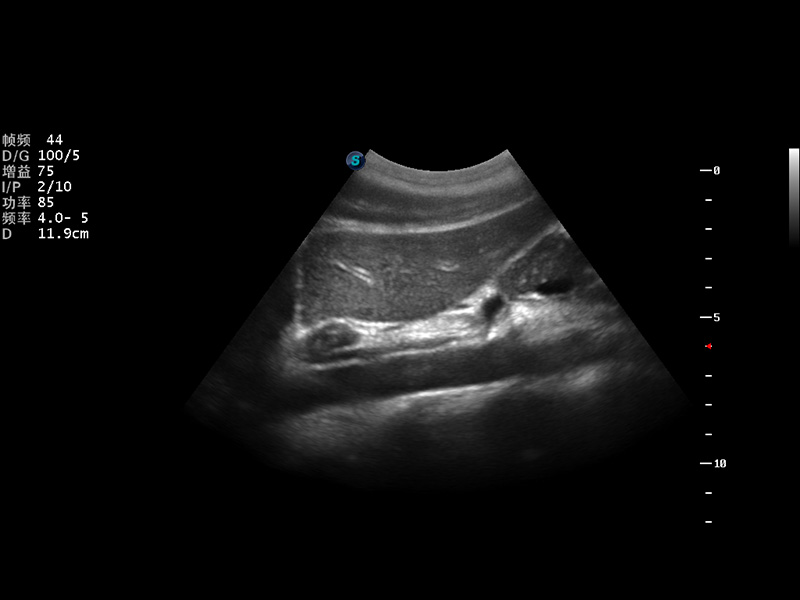

随着开立医疗超声设备核心技术的提升及临床应用领域的拓展,公司2014年全新推出全数字S12系列超声彩色多普勒诊断仪,真正意义上实现了“小身材、大智慧”的设计理念,外观小巧灵活,内在性能强大。即兼顾了全身临床应用,又拓展了多种高级成像功能,轻松满足临床应用日趋多元化的需求。

实时宽景成像